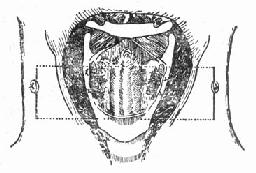

图96-3 切除会厌根部血肿

图96-4 缝合软骨外板软骨膜及甲舌膜